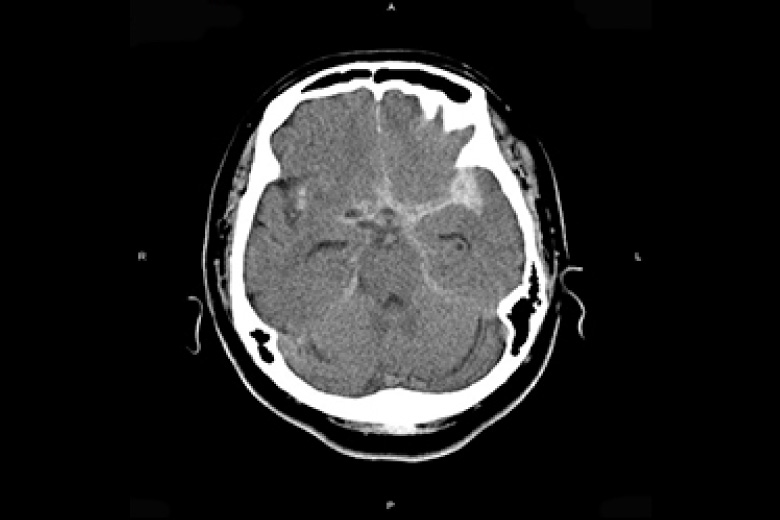

X線CT

2台のマルチスライスCT(320列、64列)にて検査を行っております。

CTはX線管と検出器が体の周りを360°回転しコンピュータ処理により画像を作成します。

頭部・胸部・腹部・四肢など全身の撮影ができ、心臓(冠動脈)などの撮影も可能です。

320列CTにより全身をより短時間で撮影できるようになり、患者さんの負担が少なくなりました。また、320列CTでは16cmの範囲(頭部や心臓など)を1回転で撮影できます。

また逐次近似再構成により被ばくの少ない検査が受けられます。

くも膜下出血